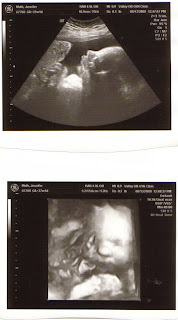

Today's OB visit included an ultrasound, to check on the size of the baby. It sure beats a glucose test any day. He/she is measuring right around 7 lbs, in the 57th percentile. (Aaron was 8bs 3oz at birth) The ultrasound tech at our office is so nice, and today she said, "You can't get much more average than that!" I got to bring home these great shots of our little one's profile and face and I looked away at the "appropriate" times. We like our surprises around here, that is for sure.

Just look at those chubby little cheeks.